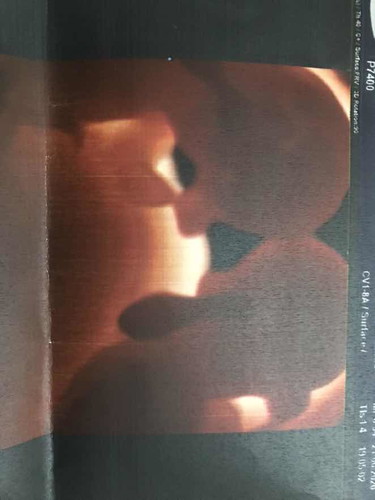

เอาลูก แฝด มาโชว์กันหน่อยจ้า

สอบถามหน่อยครับ. แฟนท้องแฝดต้องดูแลตรงไหนเป็นพิเศษบ้างครับ